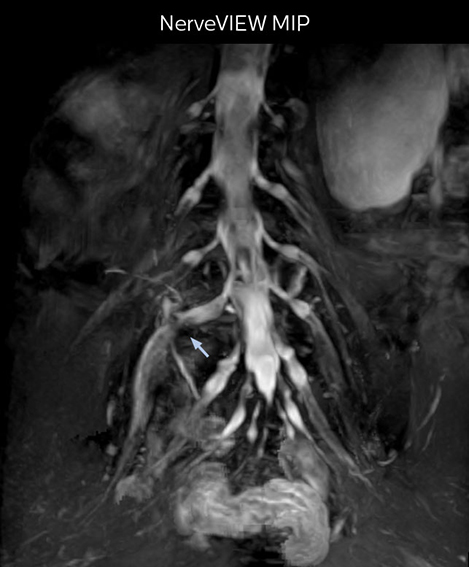

“In such case, we would then browse through axial T2-weighted MR images slice by slice and mentally reconstruct the actual situation based on both radiculography and MRI. Fortunately, NerveVIEW can now very well show nerve courses and presence of nerve compression or edema in one single image series.” “We have often seen NerveVIEW directly depict details of the nerve compression that were not observed by radiculography. Therefore, we think that with NerveVIEW we can reduce the number of invasive examinations, especially for some patients with lumbar plexus symptoms.”

“Before NerveVIEW, diagnosis by MRI alone was sometimes difficult, unless there was a strong suspicion based on clinical symptoms,” says Shoji Yabuki, MD, DMSc, Orthopedic surgeon at Fukushima Medical University School of Medicine. “This is why we routinely perform selective lumbosacral radiculography (nerve root block) and x-ray in such cases. However, radiculography can only depict nerves as far as the contrast agent reaches. When a nerve is distorted by compression, the contrast agent will not pass through this compressed area, preventing us from evaluating the full nerve compression.”

The key concept in MR neurography, Dr. Yabuki stresses, is the ability to directly visualize spinal nerves, versus inferring the presence of pathology indirectly. “Before NerveVIEW, we estimated compression of the nerve by looking for the presence or absence of fat signal on other MR images,” he says.

“For example, in sagittal images, when the presence of fat is observed in the intervertebral foramen, it suggests that there is a margin around the nerve. Similarly, the absence of fat indicates that the nerve is being compressed. So, we used to deduce nerve compression indirectly. With NerveVIEW, however, we can observe the condition of the nerves directly, regardless of the presence or absence of fat. We always prefer such direct observation of anatomy over having to make an inference about it.”

“NerveVIEW can clearly show nerve courses and presence of nerve compression. However, when multiple abnormalities are seen, it can still be hard to determine which nerve is causing the symptoms,” says Dr. Yabuki. “In our experience so far, we see abnormal findings on NerveVIEW in about 70% of elderly patients. As the pain is usually caused by only one nerve, we thus need to find the exact corresponding nerve.” “With a nerve root block, the patient's pain is improved by infiltration of local anesthesia directly around the nerve root considered to be responsible. Knowing such nerve root block findings prior to image interpretation, helps to easily recognize abnormal findings on NerveVIEW as well. In other words, without a priori knowledge, based on symptoms and/or nerve root block findings, we must be aware of the possibility of overdiagnosis.”